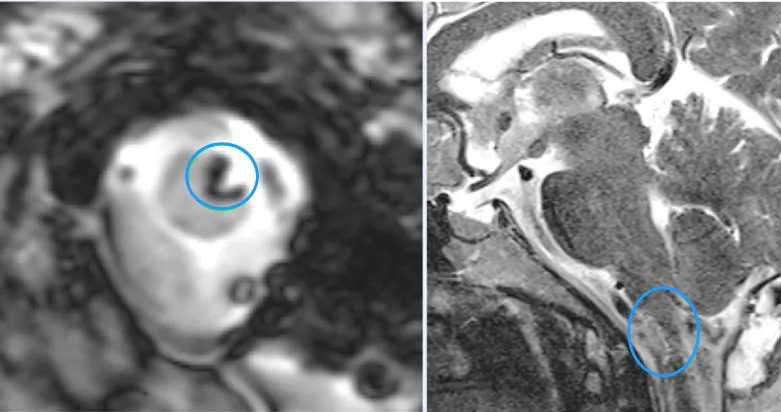

手术完没几天,就做了术后MR。跟术前的片子一对比,蓝色标记的地方能清楚看到,脑干里的病变已经全切掉了,也没有脑水肿、出血这些问题。

到了术后第10天,May顺利拆了线,就能出院了。现在她手脚的力气慢慢回来了,脸不麻了,说话也清楚多了,走路也稳当不少。之前那些让她绝望的症状,都在一点点变好。